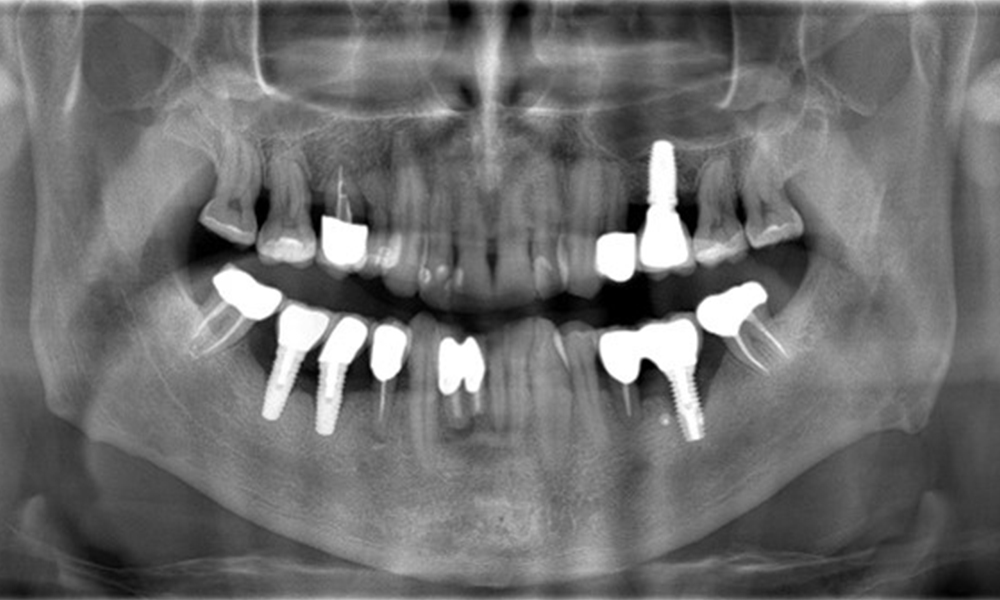

The patient has no particular risk factors with specific dental implications in his medical history. The key factor, therefore, is the requirement in terms of oral health. In this respect, there is evidence of a probing depth of 5 mm at the implant in the 3rd quadrant and, on the X-ray image, increased bone loss. The patient also has currently stable early periodontal disease and two active initial carious lesions.

The X-ray images show the progression of bone loss.

The X-ray images show the progression of bone loss. OPG from 29.06.2020 (left) and OPG from 26.02.2024 (right).